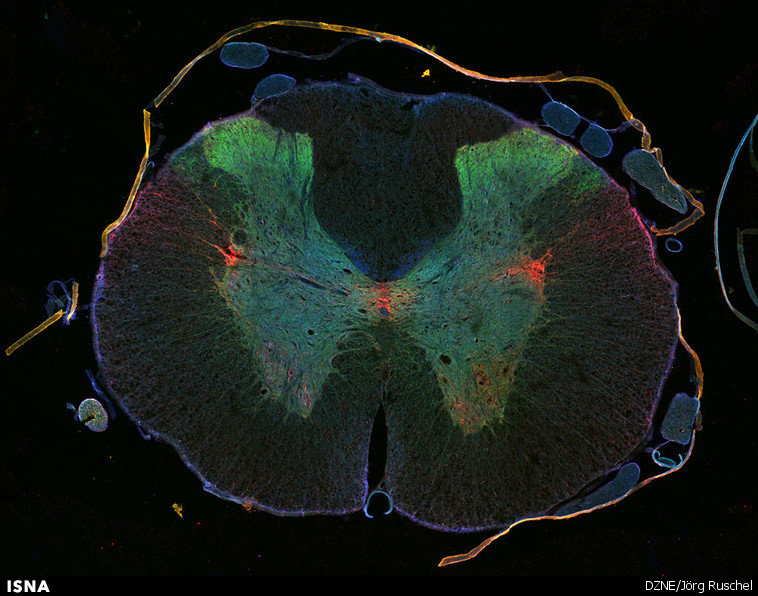

ارائه روشی جدید برای درمان آسیب‌های نخاعی

مدت‌های زیادی است که ضایعات نخاعی و عصبی عارضه‌ای غیرقابل برگشت و درمان‌ناپذیر محسوب می‌شوند، اما محققان دانشگاه دارت‌موث به تازگی روشی برای سنتز محصولات کمیاب طبیعی طراحی کرده‌اند که بازیابی و رشد دوباره سلول‌های عصبی آسیب‌دیده را امکان‌پذیر می‌کند.